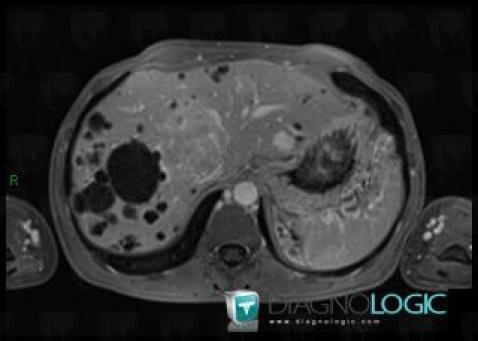

Polykystose rénale, Rein, IRM

Voici les informations spécifiques à l'image clé ci dessus:

- Diagnostic Polykystose rénale, Localisation(s) Rein, comportant les gammes Masse rénale en hypersignal T2, Masse rénale kystique, Maladie kystique rénale

- Diagnostic Polykystose rénale (lié à Kyste ), Localisation(s) Rein, comportant les gammes Masse rénale exophytique

Polykystose rénale, Foie, IRM

- Diagnostic Polykystose rénale, Localisation(s) Foie, comportant les gammes Lésion hépatique en hypersignal T2

- Diagnostic Polykystose rénale (lié à Polykystose hépatique), Localisation(s) Foie, comportant les gammes Lésion hépatique kystique